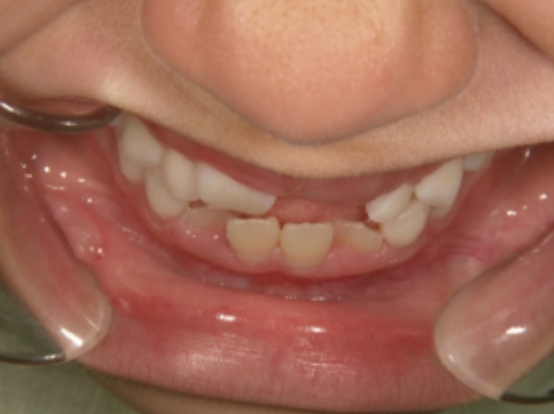

治療前① 小1:初診

治療スタート:7y4m